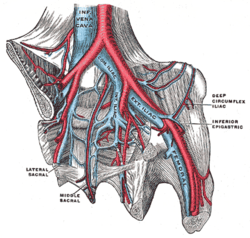

The iliac veins. (Int. iliac visible at center.) | |